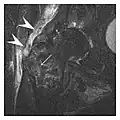

Occult osseous injuries may result from a direct blow to the bone by compressive forces of adjacent bones against one another or by traction forces during an avulsion injury. Lesions in the tibial plateau, hip, ankle, and wrist are often missed. In a tibial plateau fracture, any disruption of the posterior and anterior cortical rims of the plateau should be sought. Impaction of subchondral bone will appear as an increased sclerosis of the subchondral bone (Figure 1). In the hip, posterior acetabular fractures also present subtle radiographic findings. The acetabular lines should then be carefully examined keeping in mind that the posterior rim, which is harder to see on X-rays, is more frequently fractured than the anterior rim (Figure 2). In the wrist, detection of carpal bone fractures is often challenging, with up to 18% of scaphoid fractures radiographically occult. Carpal fractures, especially the scaphoid, are associated with the risk of avascular necrosis. In apparently normal wrist radiographs from symptomatic patients, if there is history of a fall on an outstretched hand with pain in the anatomic snuffbox, suggesting scaphoid injury, the initial examination with posteroanterior, lateral, and pronation oblique views must be complemented by other specific views such as supination oblique and the "scaphoid" view A careful examination of cortices for evidence of discontinuity or offset and cancellous bone for lucency is necessary (Figure 3).[1]

Figure 1: A 56-year-old woman presenting with left knee pain after a fall. (a) Initial anteroposterior radiograph was considered normal, however, subtle cortical disruption of the anterior rim of the medial tibial plateau, medial to the tibial spine, is noted (arrow). (b) Coronal T1-weighted MRI confirms the cortical disruption (arrow) and shows extensive fracture through the proximal tibia. (c) Coronal proton density-weighted image with fat saturation shows extensive edema in the subchondral bone. Note also hypersignal adjacent to the medial collateral ligament corresponding to a grade I sprain (arrowheads).[1]